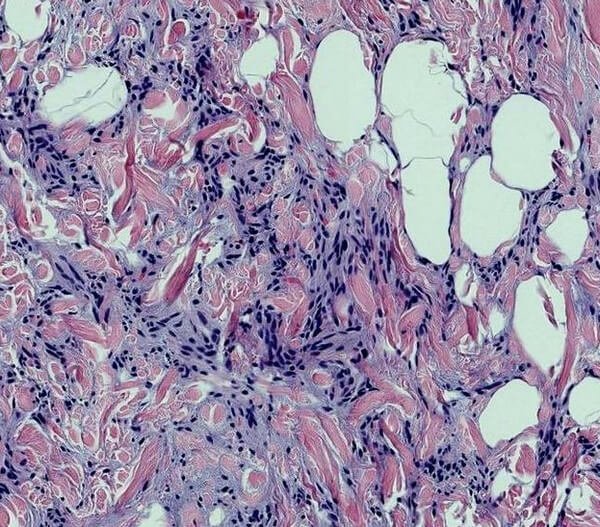

Picture 2 : Angiolipoleiomyoma

Image source : springer images